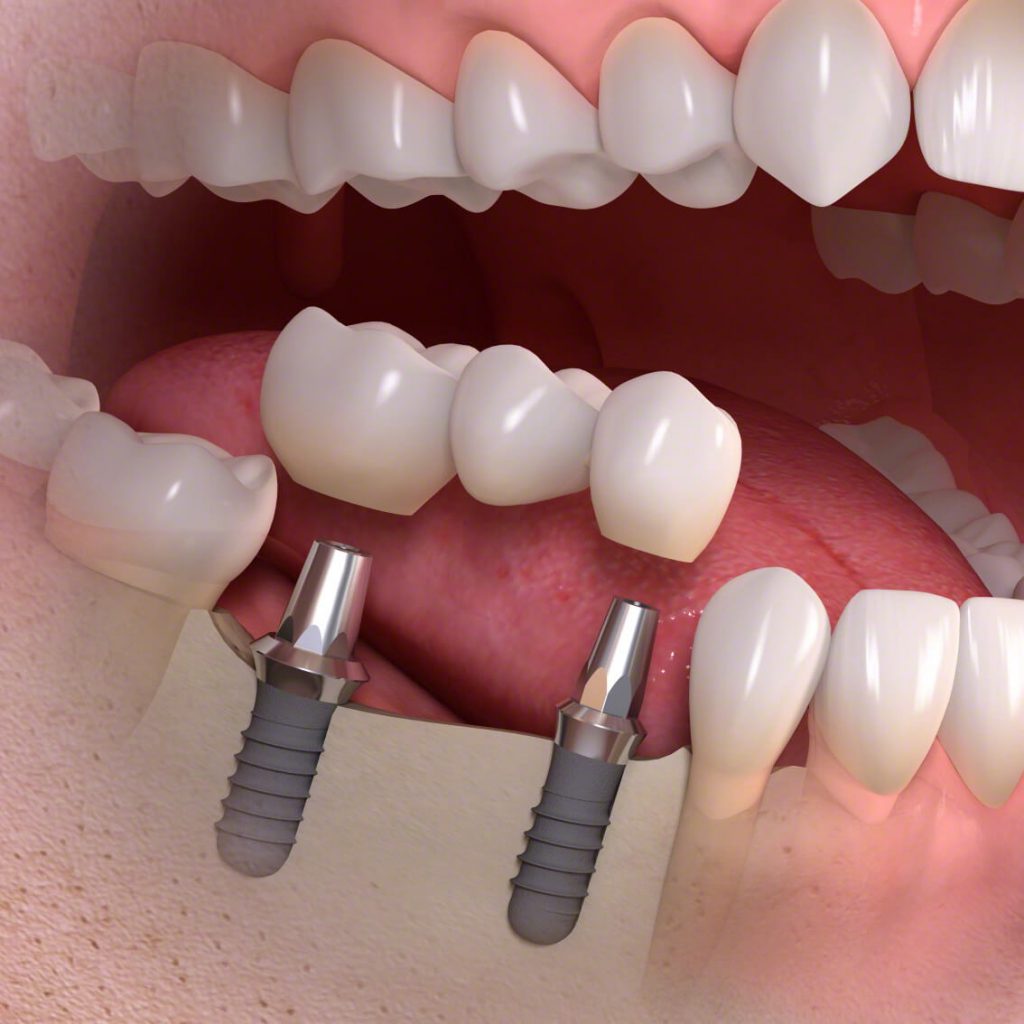

Amit a köznyelvben fog implantátumnak nevezünk, az valójában egy három elemből álló egység. Ennek részei:

- fogpótlás: az implantátum tetejére kerülő, szájban látható, hiányzó fogakat helyettesítő korona, híd, vagy kivehető fogsor.

- implantátum fej vagy közti elem: az implantátumot és a fogpótlást kapcsolja össze.

- implantátum: speciális titán ötvözetből készülő csavarmenettel ellátott műgyökér, amely a valódi foggyökeret pótolja.

Háromtagú híd megvalósítása

Ebben az esetben a két implantátum behelyezésének, az implantátum fejeknek, illetve a fogpótlás árából tevődik össze a végösszeg. A két implantátum ára fajtától függően 520 000 – 740 000 forint. A három tagú fémkerámia híd ára a szükséges implantátum fejekkel 450 000 – 600 000 forint.

A háromelemű híd megvalósítása fogászati implantációval tehát 970 000 – 1 340 000 forintba kerül.